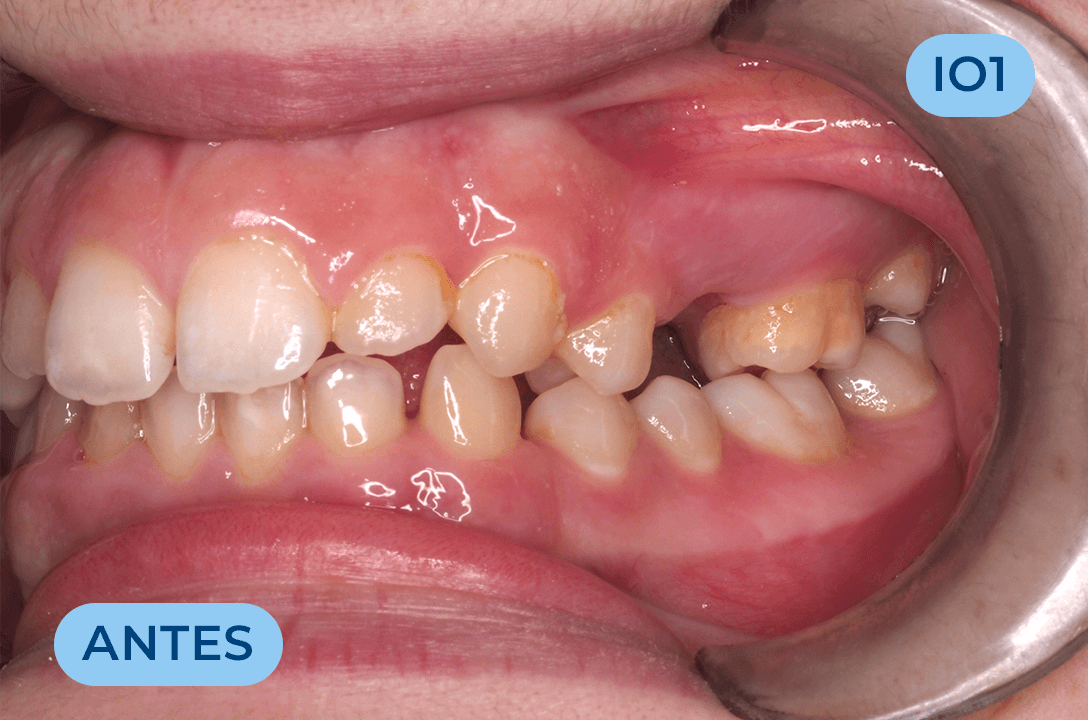

Ortodontia

É a especialidade da Medicina Dentária que se debruça sobre o estudo e correção das más posições dentárias e dos maxilares. Atualmente é possível tratar pacientes de todas as idades, no entanto a 1ª consulta deve ser realizada ainda na infância para intercetar eventuais problemas de desenvolvimento esquelético e funcional.